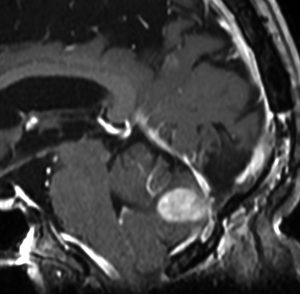

静脈洞交会 confluence に浸潤しているものです。直静脈洞は閉塞しています。右のMRIでは,ガドリニウム増強像が強弱まばらになっています。髄膜腫と診断したいのですが,ちょっと何かが違うというのがSFTです。硬膜や骨や脳に浸潤性格を有します。亜全摘出して術後に54グレイの放射線治療をしました。

5年後に小脳内に再発しました。全摘出したのですが,その後もあちこちに再発を繰り返しています。最初はグレード2でしたが,再発を繰り返すと増大速度が速くなり,再発までの期間が短くなり,多発性再発となってきます。